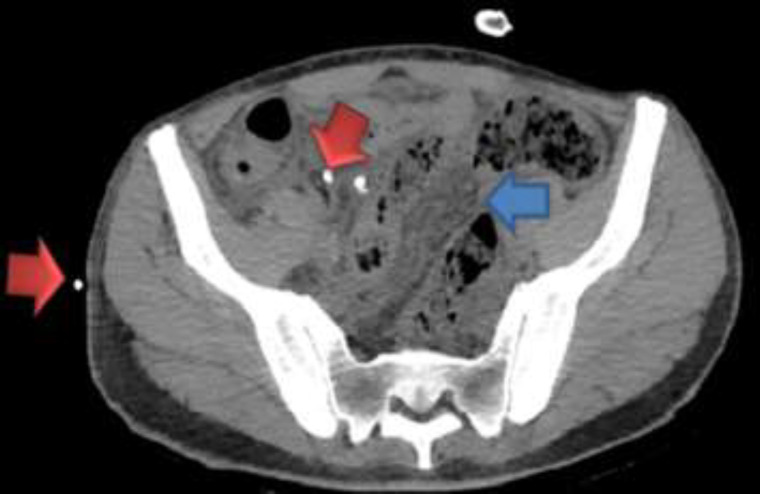

Case presentation: Herein, we present a Persian male adult who manifested with epigastric pain, weakness, and a history of pleuritic chest pain two months prior to admission. The findings of the physical examination included vital signs within the normal range, unilateral fine crackle in the lung, abdominal distension with positive shifting dullness, and fluid wave test. Analysis of the ascitic fluid revealed a Serum-ascites albumin gradient (SAAG) of less than 1.1g/dl, indicating a non-portal condition. The results of the acid-fast bacilli (AFB) staining as well as the TB polymerase chain reaction (PCR) test were negative. However, the adenosine deaminase (ADA) level was 44 IU/L. A chest CT scan revealed mediastinal lymph node enlargement and pleural thickening with loculated pleural effusion. Three acid-fast bacilli smear of morning sputum were sent, and all three were negative. An abdominopelvic CT scan showed multiple periaortic and mesenteric lymph nodes of varying sizes with mesenteric haziness and accumulation of effusion in the peritoneal cavity. Eventually, peritoneal biopsy, the gold standard, was performed, which revealed multiple granulomatous lesions and areas of caseous necrosis surrounded by Langerhans giant cells and epithelioid cells.